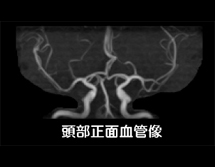

MRIは磁気共鳴画像とも呼ばれ、強い磁石と電波を使って、身体のあらゆる部位を撮影できる装置です。放射線を使用しないので被ばくの心配はなく、ラジオ波と同じ電波を利用して撮影しているため人体に優しい検査法です。 X線の画像と比べて筋肉・脊髄・内臓などが、明瞭かつ詳細に描出されます。MRIが有用なのは、脳梗塞・脳腫瘍などの脳疾患、動脈瘤などの血管障害、がん・子宮筋腫・椎間板ヘルニア・靭帯断裂など動きの小さい柔らかい組織での病変描出に適しています。 MRIの特性を利用して、造影剤を使わずに脳血管像(MRA) 胆管・膵管像(MRCP)の描出も可能です 。

実際の検査画像

| 脳血管像(MRA) | 胆管・膵管の検査(MRCP) | |